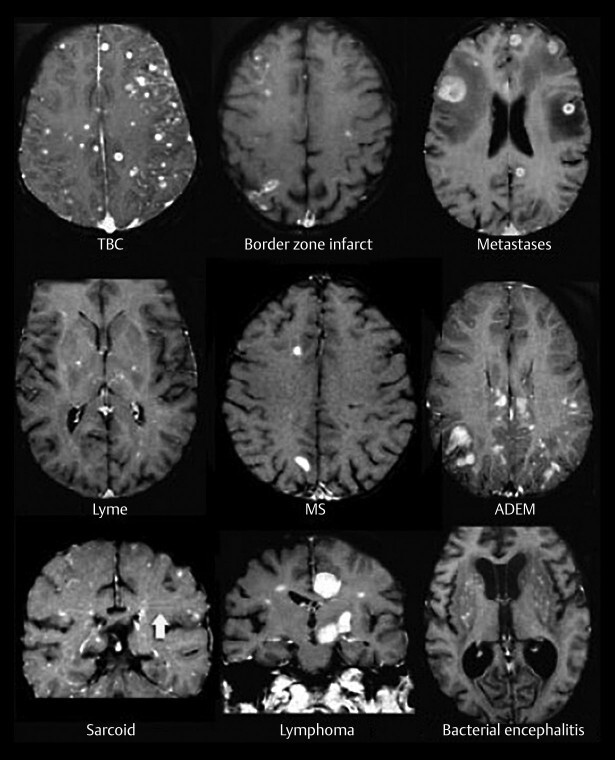

Инфекционные очаги на мрт - фото презентация